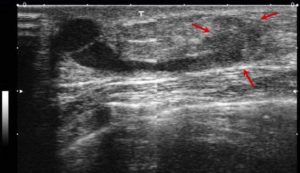

Допплерография молочной железы.Огибающий кровоток фиброаденомы

Как уже было сказано, наличие гипоэхогенного образования в молочной железе является показанием для дальнейшей диагностики с целью уточнения диагноза. Так, обнаруживает вновь образовавшиеся опухолевые структуры.

Допплеровское картирование, а также энергетическая допплерография являются высокоинформативными видами исследований. Благодаря им можно обнаружить намного большее количество опухолевых образований.

Диффузные опухоли становятся видимыми, когда имеются сопутствующие фиброзные изменения, приводящие к уплотнениям. В узловых формах фиброз наиболее выражен в центре. Цветовое допплеровское картирование может быть использовано для дифференциации сосудов от протоков, так как и те и другие имеют вид тубулярных гипоэхогенных структур.